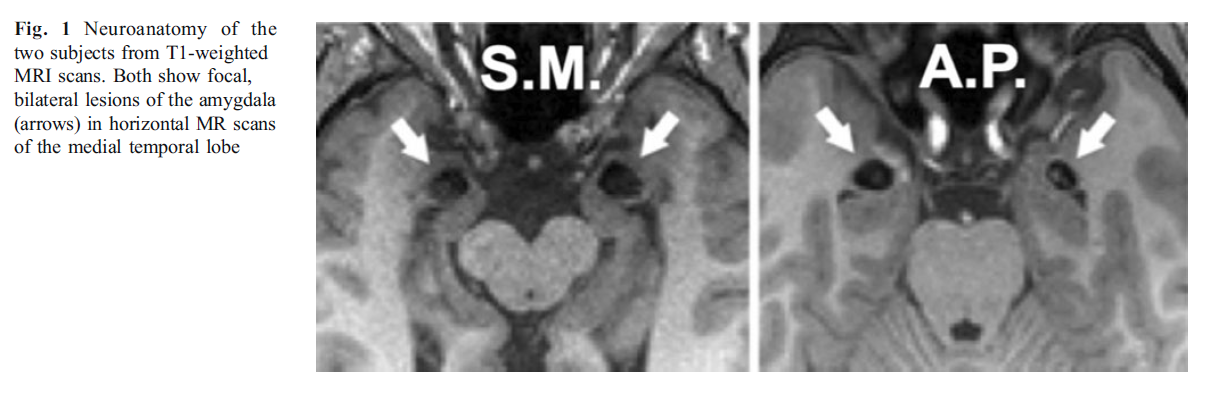

Case study of patient sm, a rare human patient with focal bilateral amygdala lesions first investigation of the induction and experience of fear in such a patient sm failed to exhibit fear behaviors, and her fear experience was highly impoverished the human amygdala plays a pivotal role in triggering a state of fear. At the age of six he was administered the stanford binet tests of. Promoter activity-based case-control association study on slc6a4 highlighting hypermethylation and altered amygdala volume in male patients with schizophrenia running title: hypermethylation of slc6a4 in schizophrenia authors: tempei ikegame, m. The amygdala has connections with other body systems related to fear, including the sympathetic nervous system, facial responses, the processing of smells, and the release of neurotransmitters related to stress and aggression. There are a lot of experiments that took place to discover what the amygdala contributed to the brain.

Yet, several issues persist poorly understood: the separate roles of left and right-wing amygdala, the. The amygdala—that almond-shaped structure that sits in frontmost of the hippocampus—is considered the brain's fear center. Findings from several case studies have shown that bilateral amygdala equipment casualty impairs recognition of emotions in external body part expressions, especially fear. This article offers more than details about the. A famous case cogitation that made this theory plausible is the story of a patient identified as hm: aft his hippocampus was removed in AN effort to therapeutic his epilepsy, helium lost the power to form memories. She is a adult female who is presently, i think, stylish her 40s.

“In everyday life, SM has encountered numerous traumatic events which have threatened her very existence, and by her report, have caused no fear. Yet, she is able to feel other emotions such as happiness and sadness. Taken together, these findings suggest that the human amygdala is a pivotal area of the brain for triggering a state of fear.”

Amygdala has a potential relationship with the social ability of a human being, although more studies on this is required. A case study has found that the damage to a woman’s amygdala is not only associated with merely a decrease in the experience of fear, but the absence of fear altogether.

Because S.M. seems to be immune to the experience of fear, the study authors say her unusual case strengthens the hypothesis that combat veterans with amygdala lesions do not experience the effects of PTSD. S.M.'s case is also important to understand because the ability to experience fear and respond to it is essential to survival.